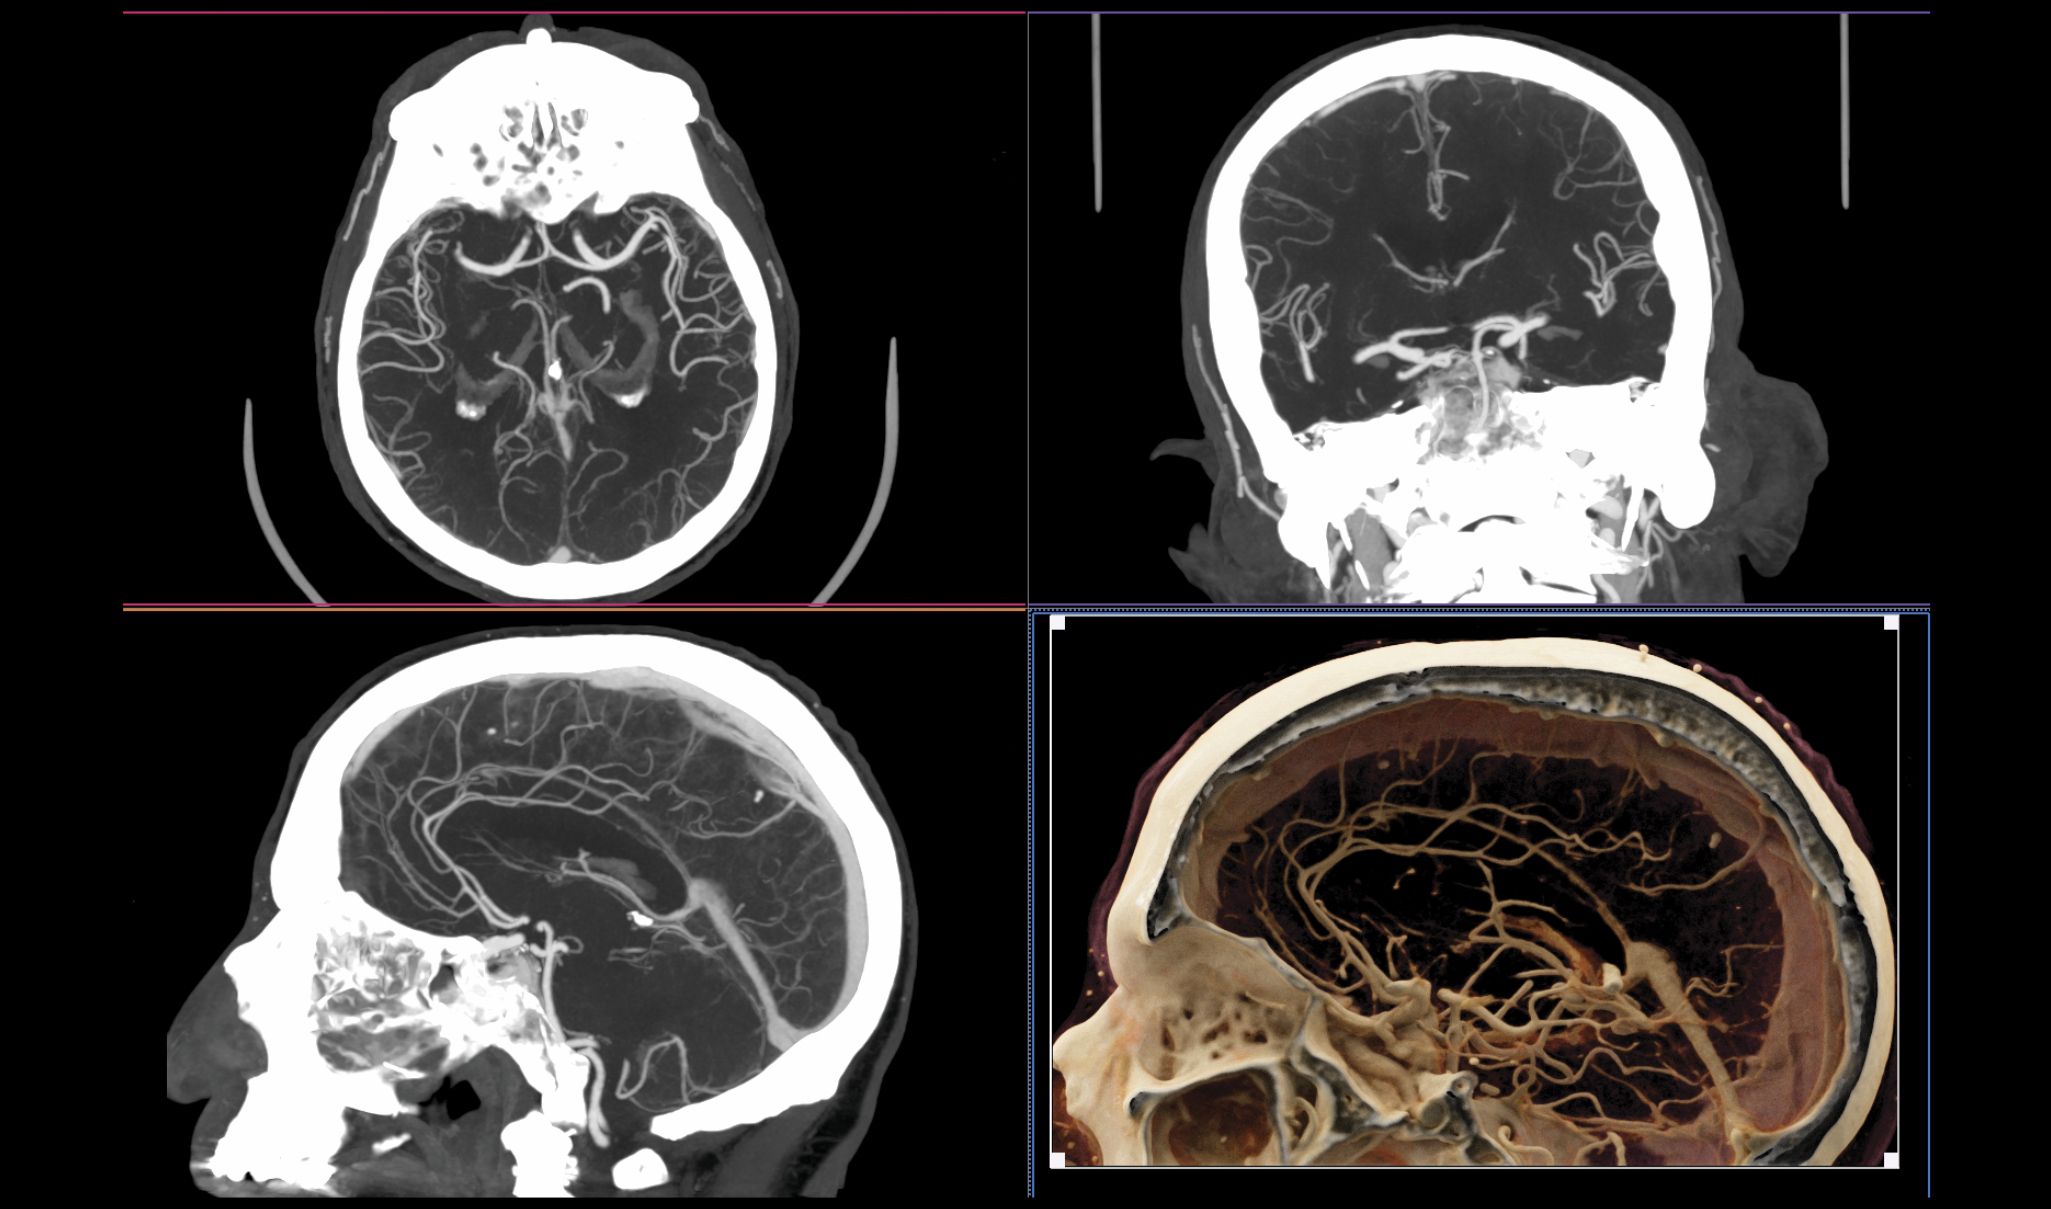

Blood vessels in the brain. Once referred to as CAT (computed axial tomography) scanners because the data were acquired and reconstructed in the axial plane, modern CT systems have submillimeter detector pixels along the

Image courtesy of Hiroshi Moriya, MD, PhD, Ohara General Hospital, Japan.